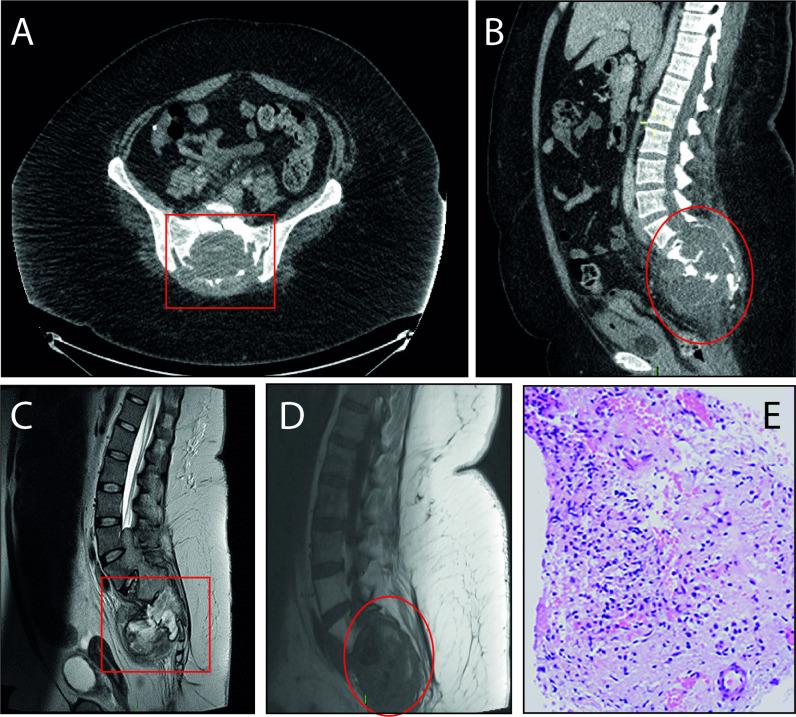

Posterior fossa ependymomas (PFEs) are designated histologically as low-grade neoplasms. Despite being characterised as benign, cases of metastasis have been reported only a few times with the patients concurrently diagnosed with the primary tumour. Interval drop metastasis or spontaneous second distal tumours are extremely rare and, in most cases, are diagnosed within a few months of primary tumour resection. Here, we report a patient with a grade 2 paediatric PFE exhibiting a 20-year interval to a second sacral ependymoma. The patient was initially diagnosed with a PFE at the age of 10 years and underwent tumour resection and postoperative radiotherapy. In their late 20s, the patient presented with basilar artery occlusion complicated by life-threatening epistaxis. Post-thrombolysis, the patient presented with a large sacral grade 1 myxopapillary ependymoma with cauda equina syndrome-like symptoms. Here, we present a rare case of two ependymomas with a 20-year interval in the same patient with compounding comorbidities.

后颅窝室管膜瘤(PFEs)在组织学上被指定为低级别肿瘤。尽管被认为是良性的,但只有少数情况下报告了转移病例,且这些患者同时被诊断出患有原发性肿瘤。间隔性滴状转移或自发性第二远处肿瘤极为罕见,在大多数情况下,在原发性肿瘤切除后几个月内被诊断出来。在这里,我们报告了一例 2 级小儿 PFEs 患者,其在 20 年后出现第二例骶骨室管膜瘤。该患者最初在 10 岁时被诊断为 PFEs,并接受了肿瘤切除术和术后放疗。在 20 多岁后期,该患者出现基底动脉闭塞,伴有危及生命的鼻出血。溶栓后,患者出现了大的骶骨 1 级黏液乳头状室管膜瘤,伴有马尾综合征样症状。在这里,我们报告了一例罕见的 20 年前同一患者出现两种室管膜瘤的病例,且该患者合并有多种合并症。